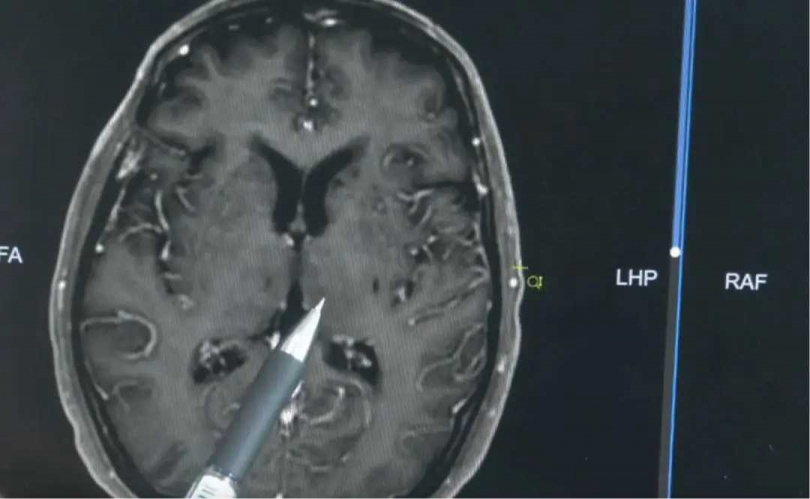

廣東72歲明叔因感染豬鏈球菌腦膜炎住院,雖然經治療後病情穩定,但雙耳聽力已無法恢復。(圖/翻攝自廣州日報,下同)

根據《極目新聞》與《廣州日報》報導,明叔家人指出,他一向身體硬朗,目前仍飼養約30頭豬。然而不久前,他突然感到身體不適,說話含糊、語意不清。家人緊急送他至鎮上醫院,最初還能簡單對話,但病情迅速惡化,意識模糊、聽力喪失。轉院至廣州後,醫師從其腦脊液中檢出豬鏈球菌,確診為急性腦膜炎。

廣州收治醫師解釋,豬鏈球菌為豬隻常見病原體,感染途徑多為皮膚傷口接觸生豬肉、宰殺病豬或食用未煮熟的豬肉等。醫師強調:「該病起病迅速,病死率高,若不及時治療,恐危及生命。」本案中,病菌已侵犯大腦聽覺區域,導致明叔雙耳永久失聰。